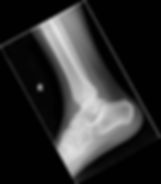

Patient is a 23 year-old female presenting with right ankle pain after tripping over her boyfriend's dog. The patient does endorse alcohol involvement, and has been unable to ambulate on her right leg. She has normal pulses, strength, and sensation distal to her ankle. Images of her ankle are seen below:

Her ankle radiographs are seen below:

1) What is this patient's orthopedic injury?